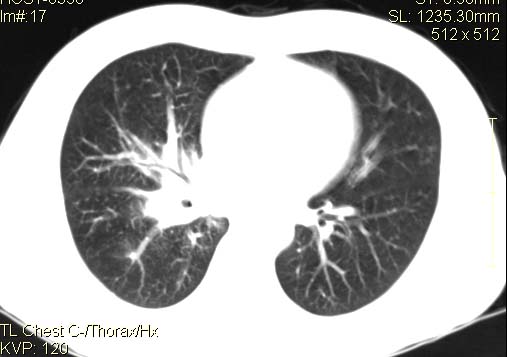

以下是引用qc80012345在2007-4-17 12:33:00的发言:[br]右肺下叶周围型肺癌伴肺门及纵隔内淋巴结转移;比较清楚。

以下是引用qingyuan在2007-4-17 14:19:00的发言:[br]右肺下叶外侧后段胸膜下区节结样病变、分叶、内可见空洞,壁厚薄不均,胸膜凹陷、肺门周围区纹理增粗、僵硬、并近似小结节样改变,肺门区软组织节结、纵膈淋巴结肿大,患者病史长、抗炎治疗无好转炎性改变基本排除,考虑:右肺下叶周围型肺癌伴纵膈及右肺门区淋巴结转移、肺内淋巴管受侵。